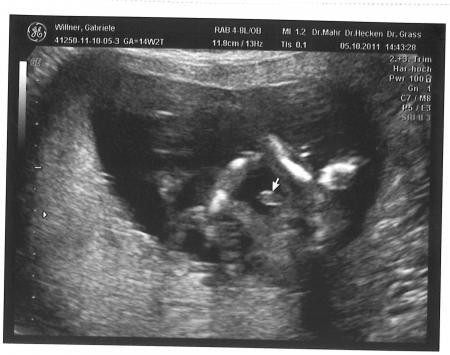

deutlich genug? LG Jordan

Bild zu